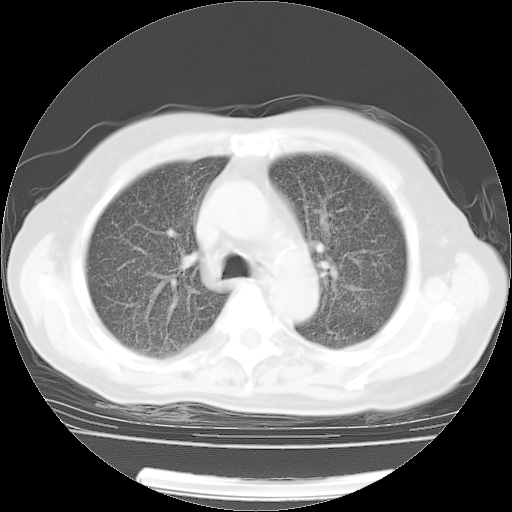

4月14日肺部CT